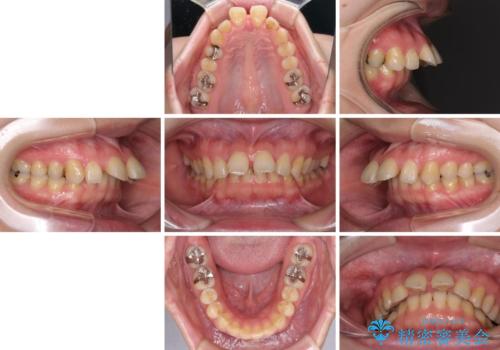

外科手術が必要と言えるほど突出した前歯 長期間をかけた抜歯矯正

- 上下の前歯が接触しないくらいに突出した上顎前歯を気にして来院された患者様です。

上顎が前方に傾斜して突出しており、下顎前歯は上顎の歯肉に咬みこむような、前後に大きなズレがあり非常に深い咬み合わせとなっていました。

根本的な解決には上顎骨を切除する外科矯正を検討するべきですが、手術無しでの治療をご希望とのことで、上顎左右の第一小臼歯を抜歯してワイヤー装置にて矯正治療を行うこととしました。